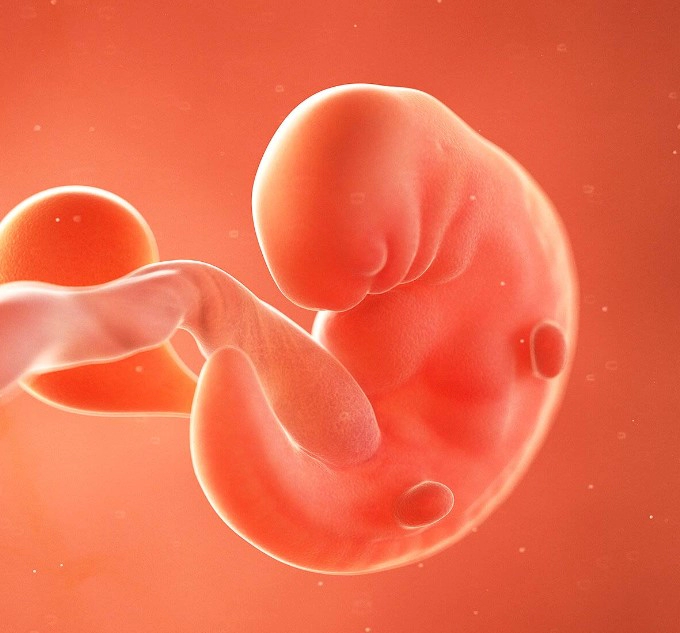

태아의 크기

임신 6주차에는 태아가 매우 빠르게 성장합니다. 이 시점에서 태아는 약 46mm(0.160.24인치) 정도의 크기로, 작은 렌즈콩 정도의 크기에 해당합니다. 이 단계에서 태아는 '배아'에서 '태아'로 분류가 변경되며, 이는 인체의 주요 기관이 형성되기 시작하기 때문입니다.

태아의 발달

이 시점에서 태아의 심장은 간단한 형태로 만들어지기 시작하며, 심장 박동도 감지될 수 있습니다. 또한 뇌, 척수, 신경계, 위, 간 등의 주요 기관도 형성되기 시작합니다. 또한 극미량의 피가 순환하기 시작하며, 얼굴, 입, 귀, 코 등이 형성되기 시작합니다.